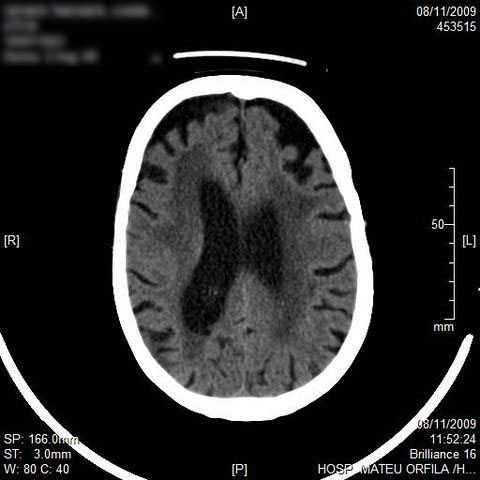

AVC amplio de territorio de A. cerebral media